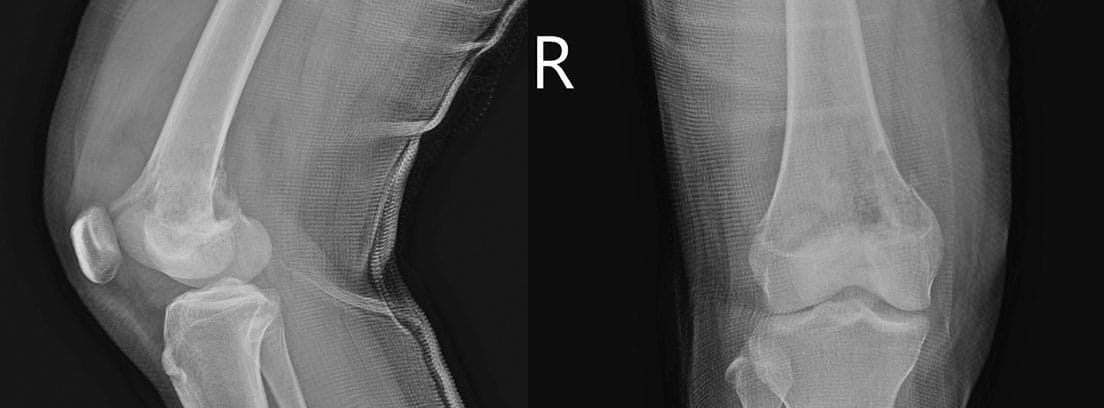

- Radiología simple: una radiografía nos puede mostrar una lesion osteolítica (destructora de hueso), que puede llegar al periostio (zona superficial del hueso) e incluso hasta los tejidos blandos. Puede observase una lesión en “capas de cebolla”.